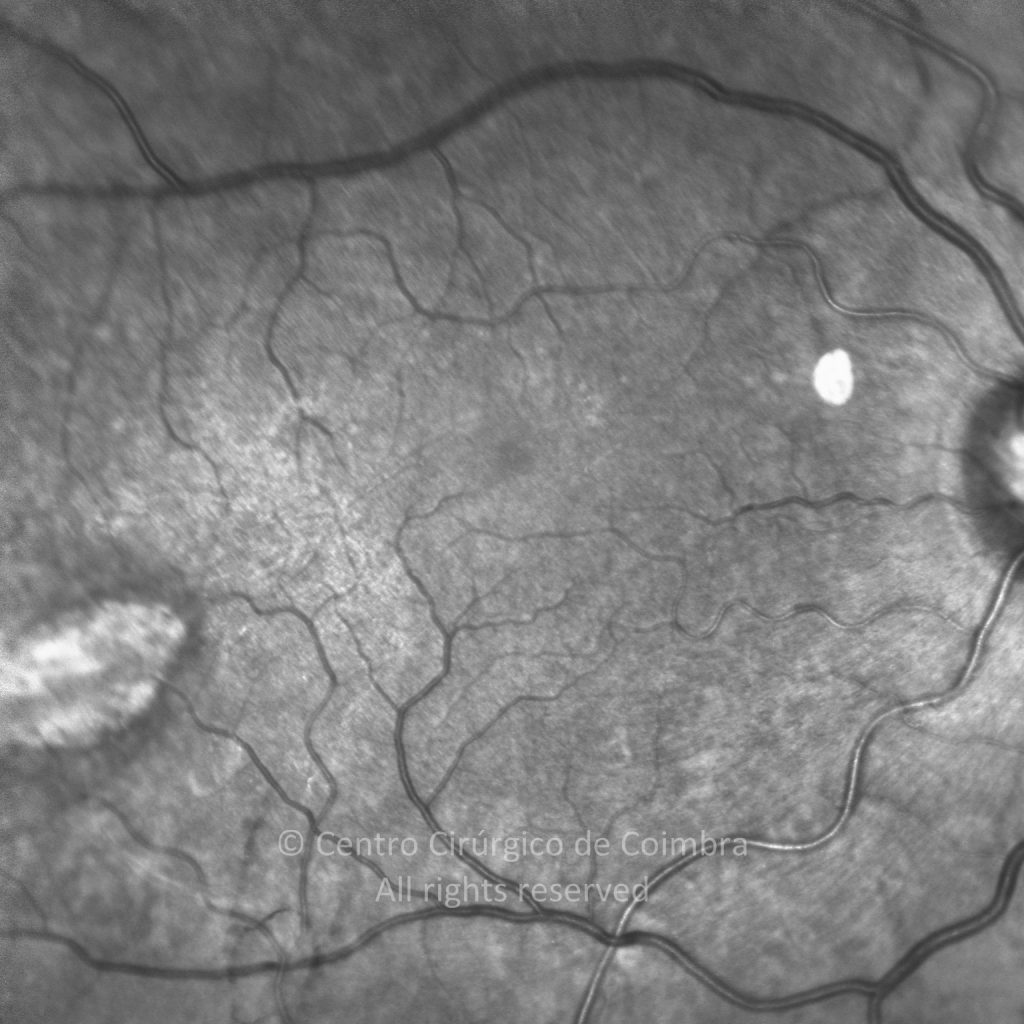

Traumatismo con un clavo en el ojo derecho hace unos 20 años, con perforación de la córnea y del iris. Catarata traumática. MAVC: 20/60 OD; OI ambliope.

Retinografía color

Cicatriz temporal. Antecedentes de vitrectomía con vítreo inferior no removido.